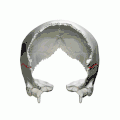

- Parietal bones (above) and temporal bones (below).